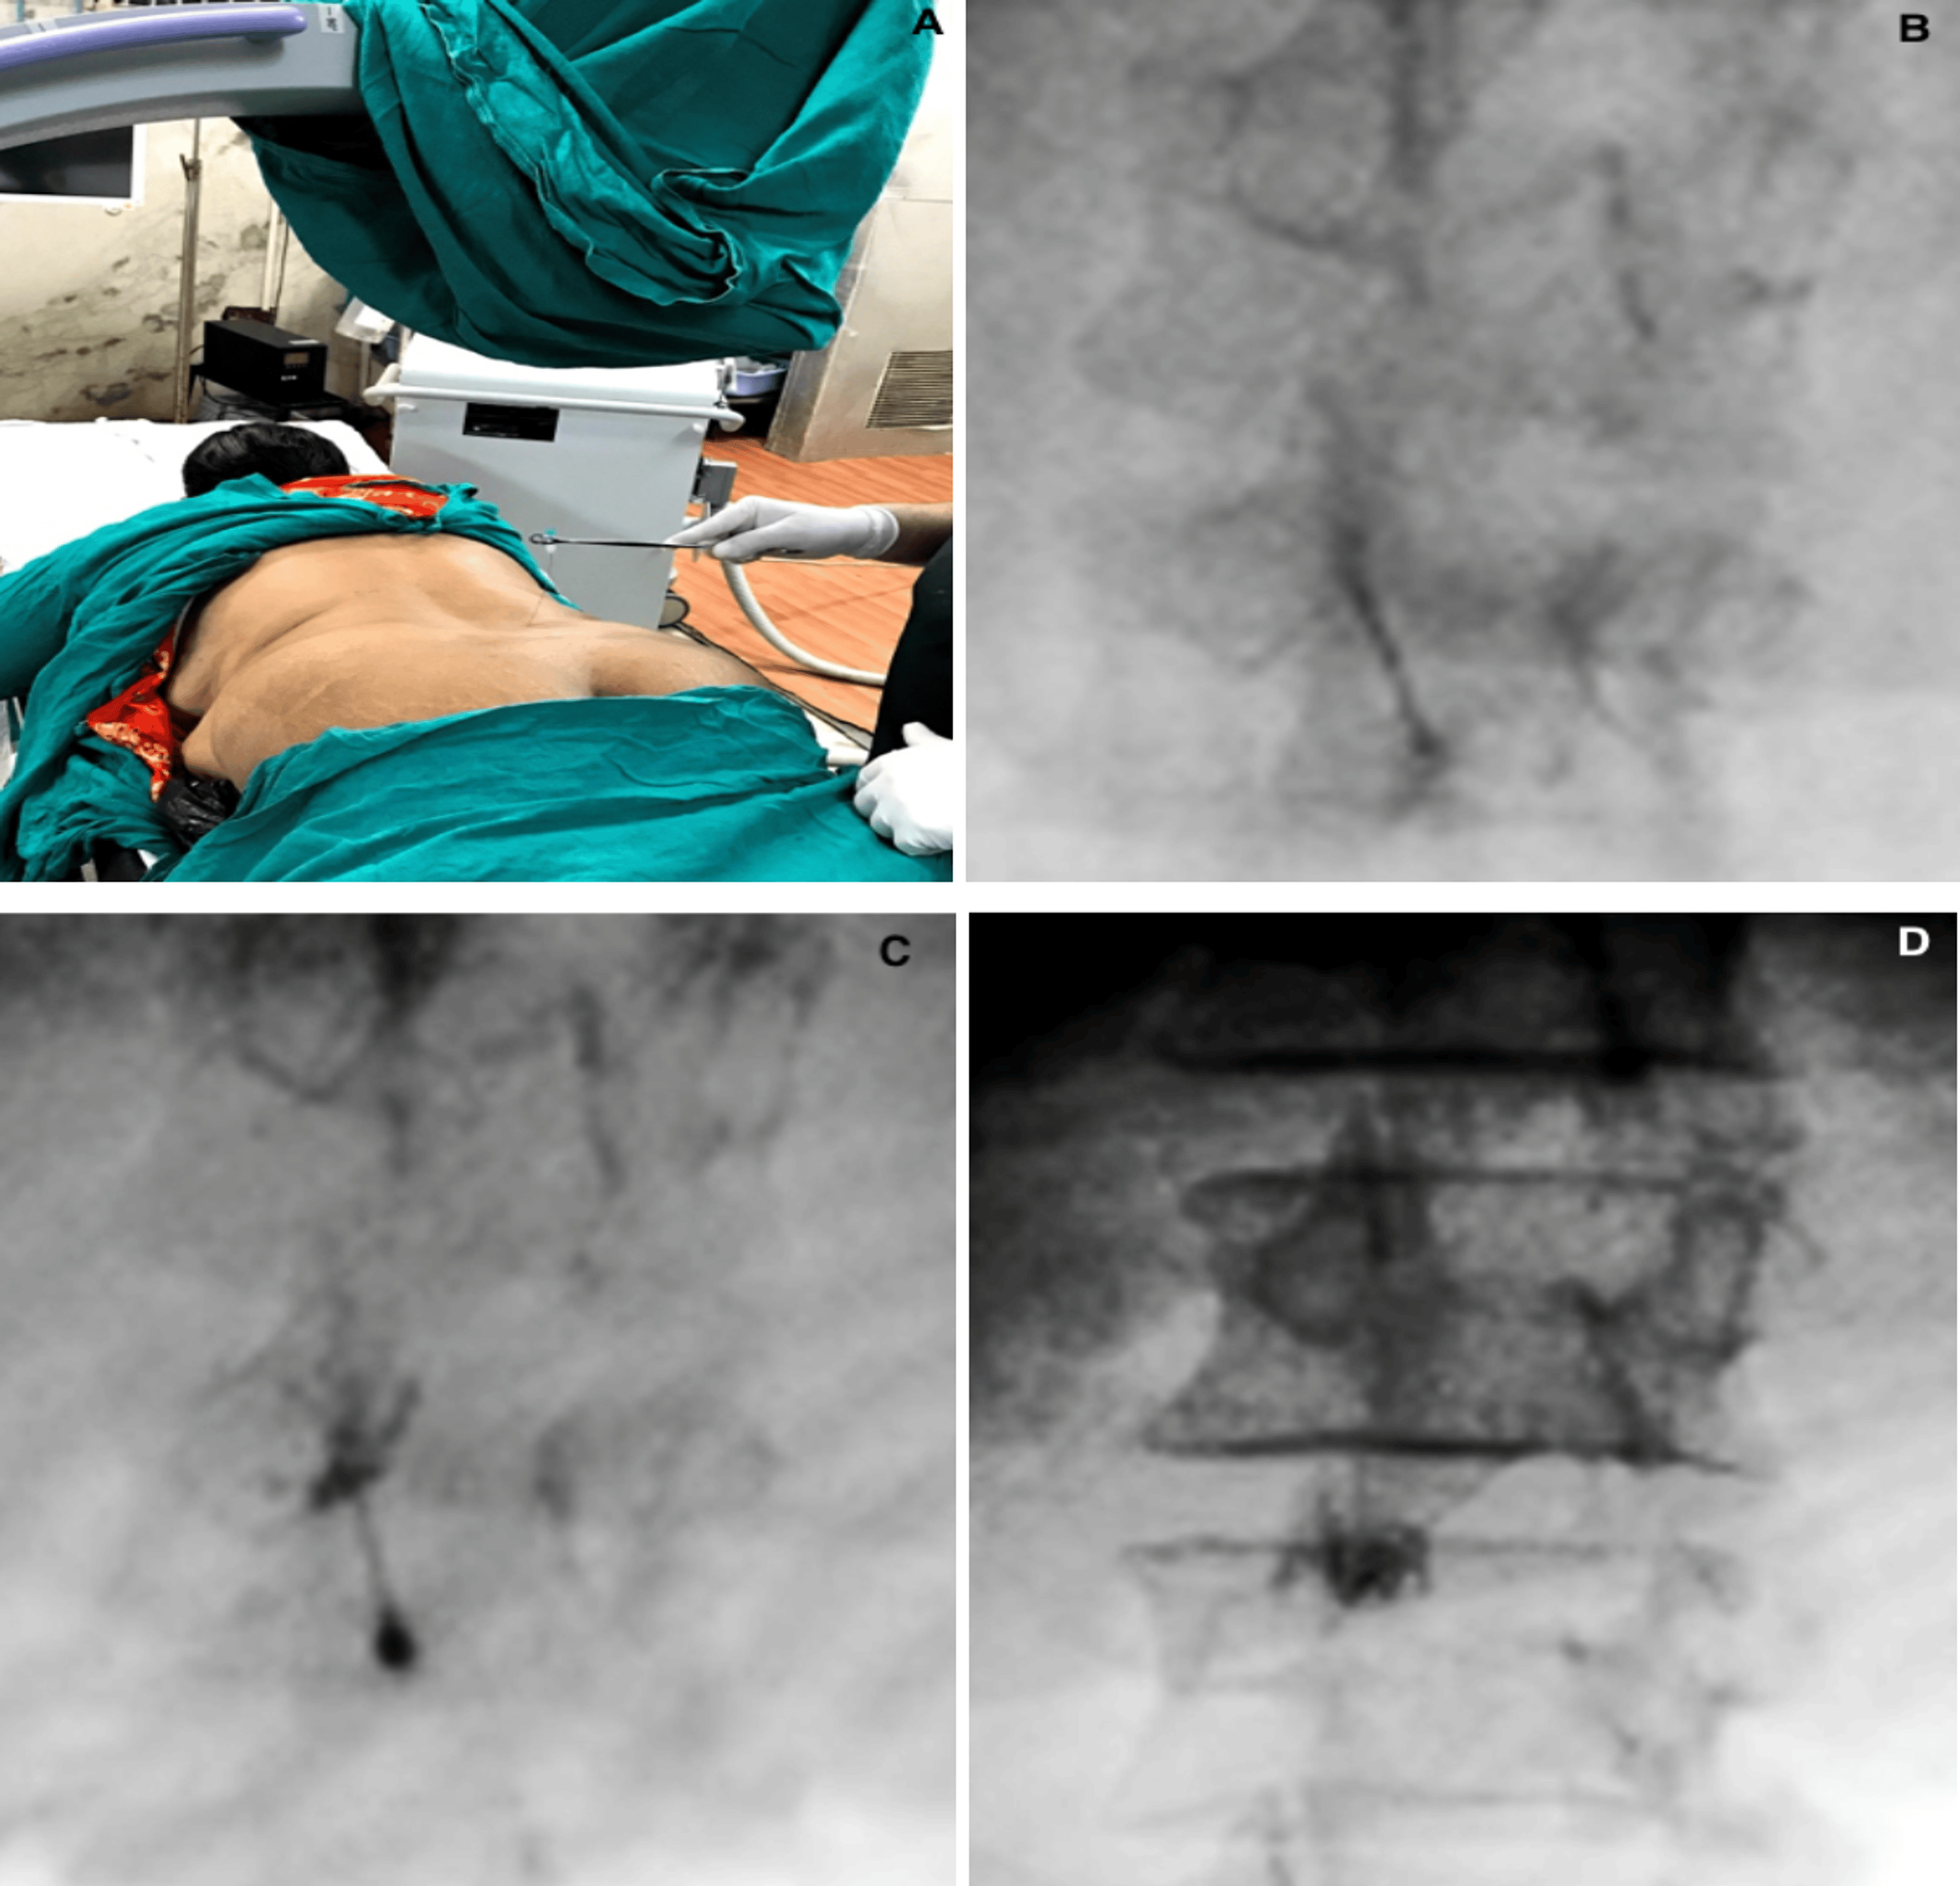

Cervical Medial Branch Block in Pain Clinic Sydney PainMed

Ultrasound versus fluoroscopyguided cervical medial branch block for Facet Joint Vs Medial Branch Block Your facet joints are small pairs of joints that. what is a medial branch block? While facet joint injections are given directly into the facet joint, medial branch blocks target the medial branch nerves that carry pain signals from the facet joints to the brain. a medial branch block is a test to see if neck and back. Facet Joint Vs Medial Branch Block.